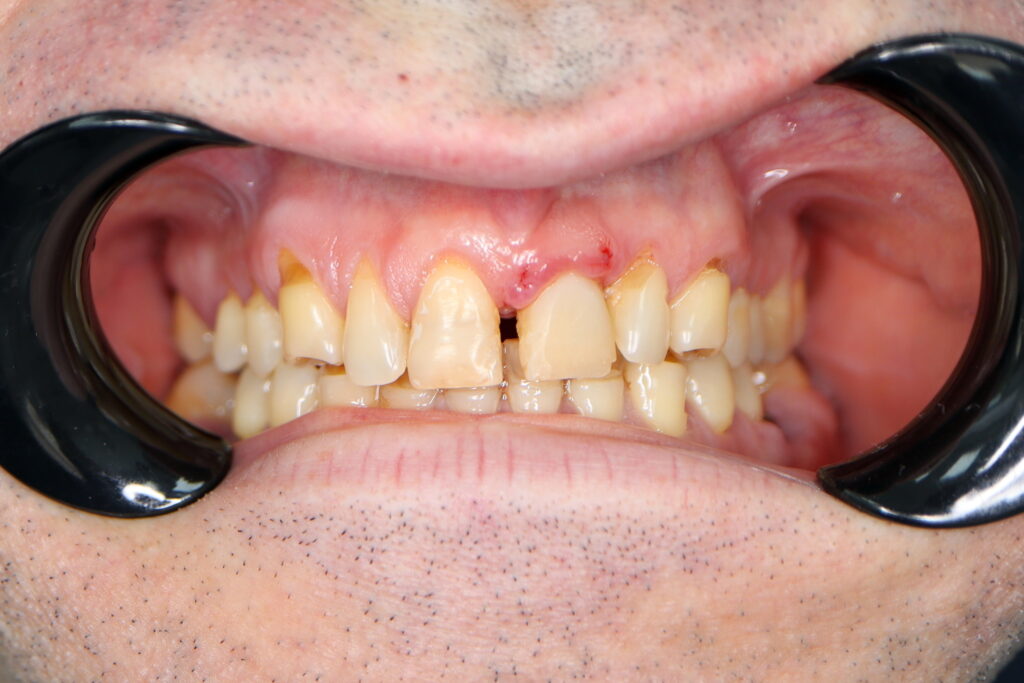

Ситуация до лечения

Пациент обратился с жалобами на эстетические недостатки.

Диагноз: Частичная адентия, клиновидные дефекты, гипоплазия эмали.

пациент до имплантации

Сложность данного ортопедического лечения заключалась в наличии диастемы(щель между центральными резцами).